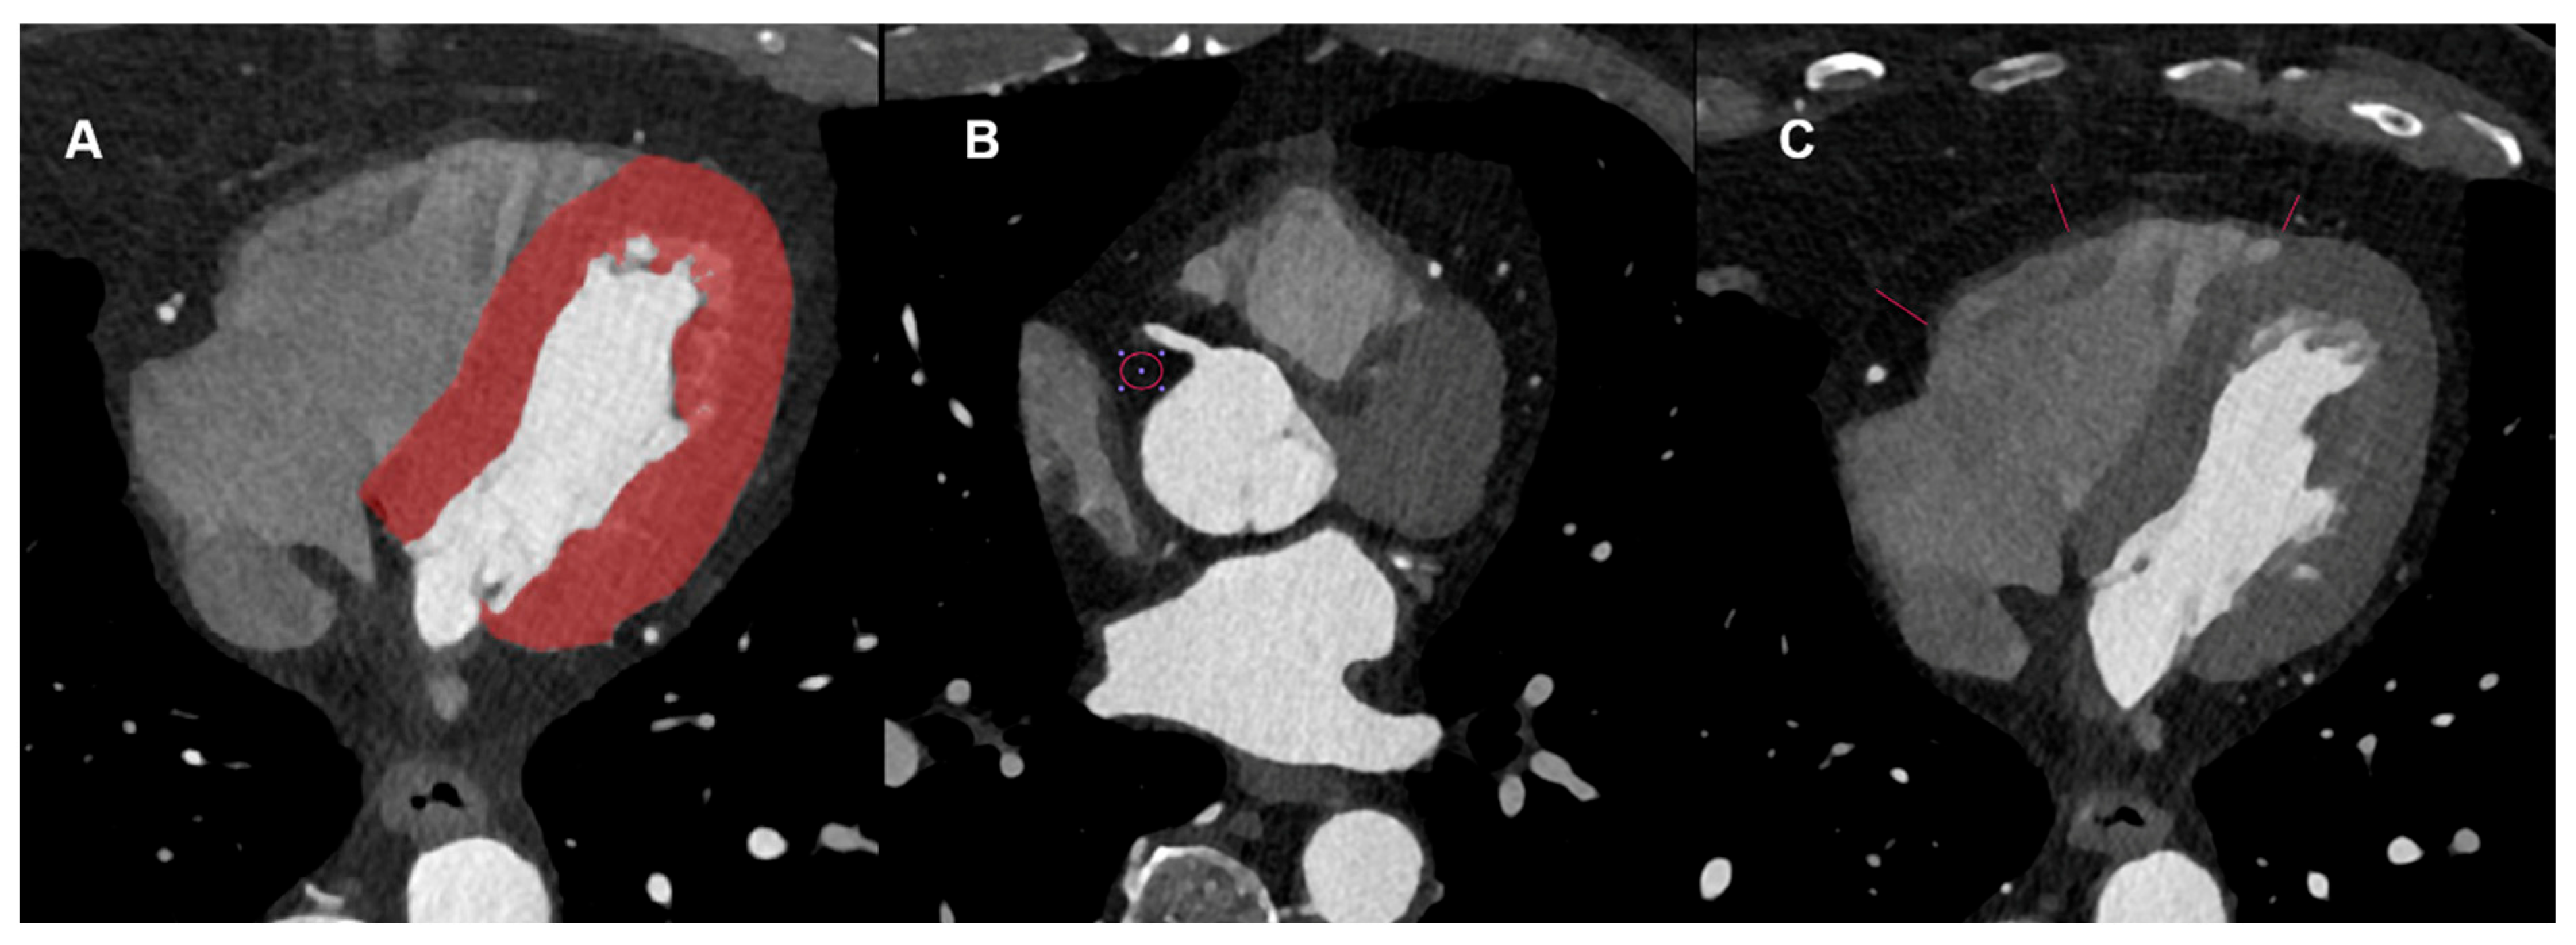

2.3. Cardiac CT Image Analysis

2.4. Radiomics Feature Extraction